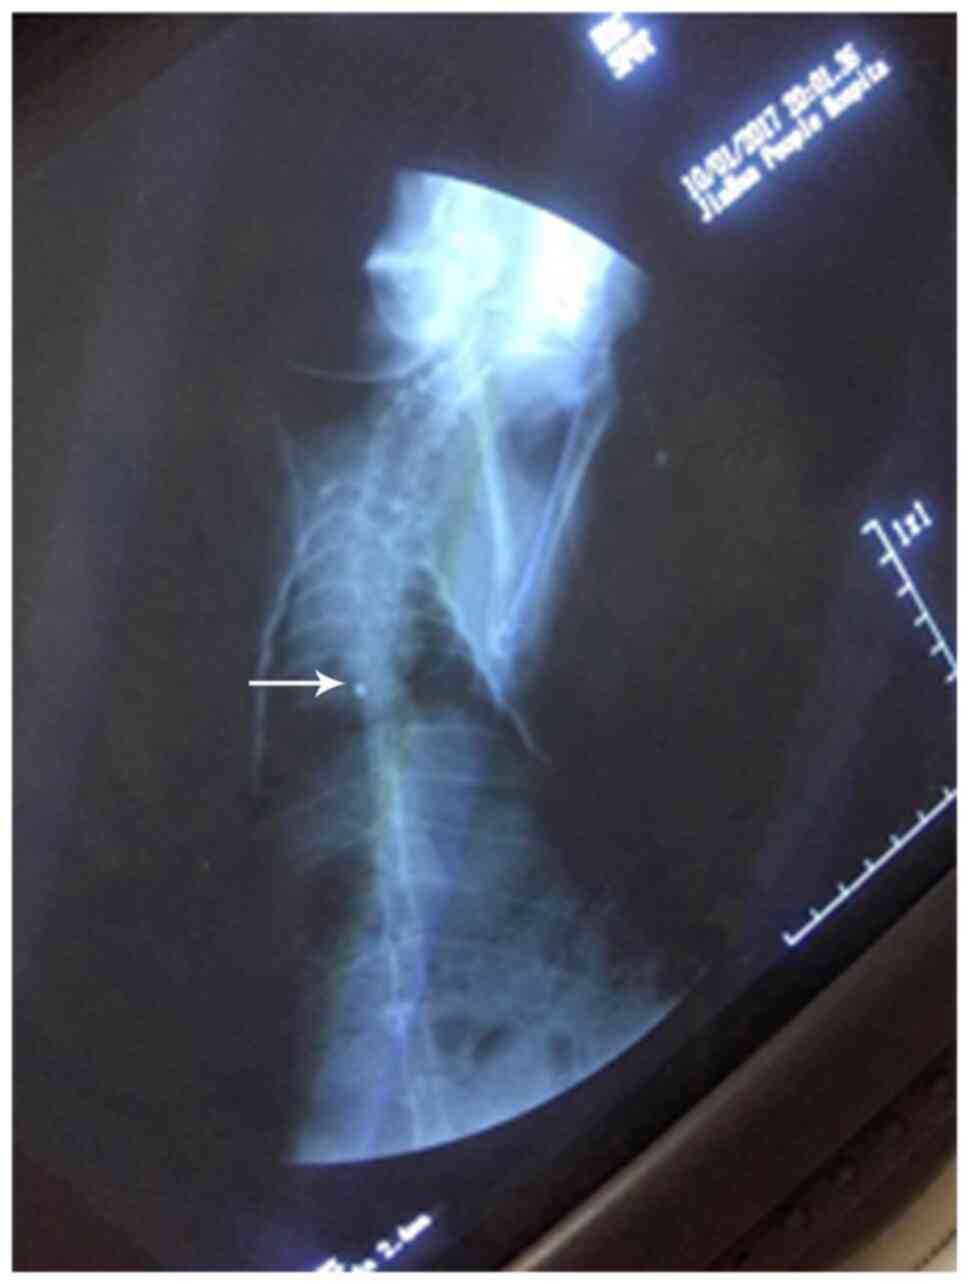

Evaluation of PICC models

The criteria for evaluating the successful establishment of PICC models were as follows: i) The established animal model of PICC was successful with one puncture; ii) there was no local damage or bleeding in the puncture; iii) the end of the catheter was not twisted or folded under X-ray fluoroscopy; and iv) the PICC tube was placed in the anterior vena cava. As presented in Fig. 2, the transparent dot corresponded to the end of the catheter.

Figure 2

X-ray fluoroscopy of the PICC tube. X-ray demonstrated that the end of the PICC tube reached the anterior vena cava of the rabbit. Arrow indicates the transparent dot that highlights the end of the catheter. PICC, peripherally inserted central catheter.

Construction of a PICC chemotherapy rabbit model

In the present study, a PICC chemotherapy model was successfully established in 48 rabbits. To observe the pathological changes of the puncture point during PICC catheterization, the rabbits were randomly separated into eight experimental groups. A course of chemotherapy includes 2-3 cycles (19); the present study was based on two cycles. X-rays were captured to confirm that the end of the catheter was not twisted or folded, and was placed in the anterior vena cava (Fig. 3). In each group, the local puncture site displayed no injury or bleeding. Thus, it was determined that the PICC models were successfully constructed.

Figure 3

X-ray imaging determination of successful peripherally inserted central catheter model construction. The end of the catheter was not twisted or folded, and it was placed in the anterior vena cava. Arrow indicates the catheter.